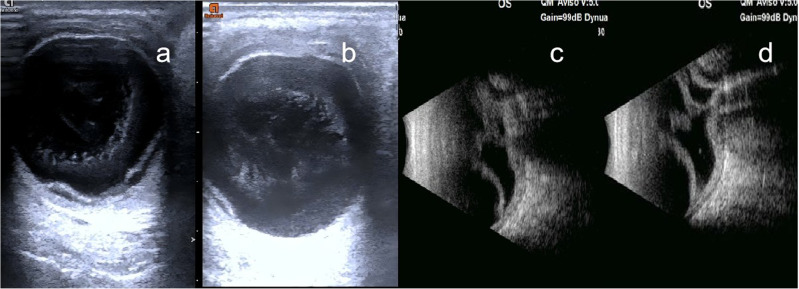

Purpose: Ocular injuries caused by wasp stings are rare but potentially devastating. This report describes a case of severe retinal and choroidal detachment secondary to corneal wasp envenomation, with a focus on pathogenesis and management challenges.

Case presentation: A 63-year-old female sustained a left corneal wasp sting, progressing to corneal edema, hypopyon, retinal-choroidal detachment, and eventual light perception loss. Despite medical therapy (topical corticosteroids, antibiotics), the patient declined surgical intervention, ultimately resulting in evisceration.